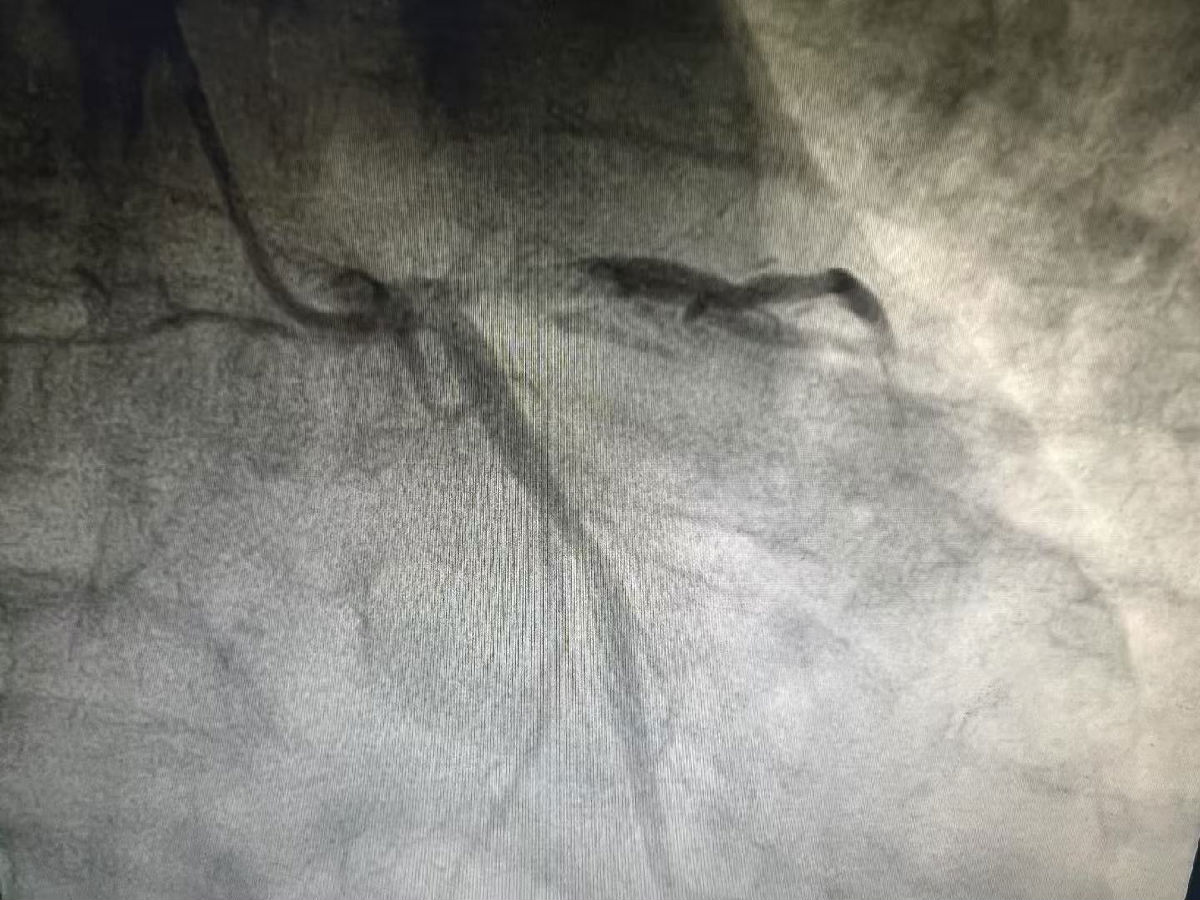

在主动脉球囊反搏(IABP)的保驾护航下,心脏介入团队立刻进行冠脉造影。结果显示,心脏最关键的主干血管--左主干末端已被大量血栓完全堵塞。这是最为危重的心梗情况,死亡率极高。面对“生命主干道”的堵塞,医护团队沉着应对,争分夺秒。采用血栓抽吸、球囊扩张、冠脉内溶栓等一系列操作,像精准的“管道工程师”一般,一点一点地清除血栓,疏通血管。

尽管仍有部分血栓影,但血流已恢复至理想的TIMI3级。为确保患者安全,经验丰富的团队当机立断,决定先稳定情况,择期再处理。这场关键手术,仅用了20余分钟!而从患者入院到导丝通过堵塞血管的D-to-W时间,更是仅用了53分钟,远低国际标准(≤90分钟)。